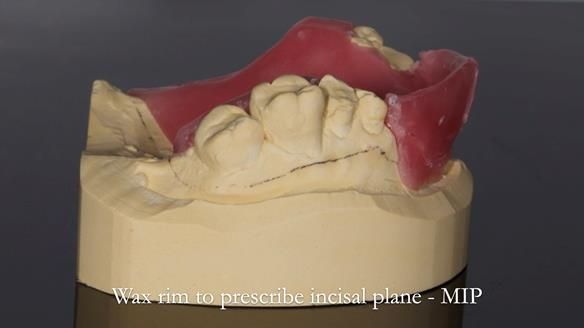

1. Denture design: A custom cobalt-chromium framework was Scandinavian-designed to maximise stability, protect the remaining teeth, and allow for future additions if needed.

3. Definitive alginate impression in custom tray: Used to ensure a well-fitting RPD.

I also used the Dahl concept to re-establish the occlusion upon fitting the RPD, which helped to intrude the lower left canine without needing to grind it too much.